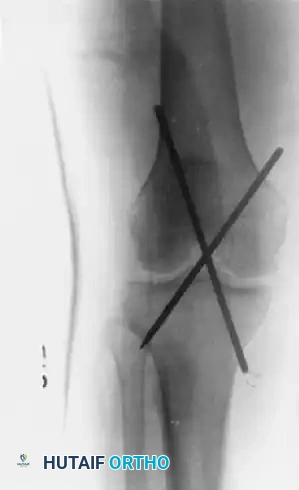

The following radiographs demonstrate the successful application of transarticular pins for temporary extraarticular fixation during the repair of torn lateral ligaments.

Figure 60-5: Radiographs demonstrating transarticular pins. (A) Anteroposterior view and (B) Lateral view illustrating the temporary extraarticular fixation with Kirschner wires utilized during the repair of torn ligaments.